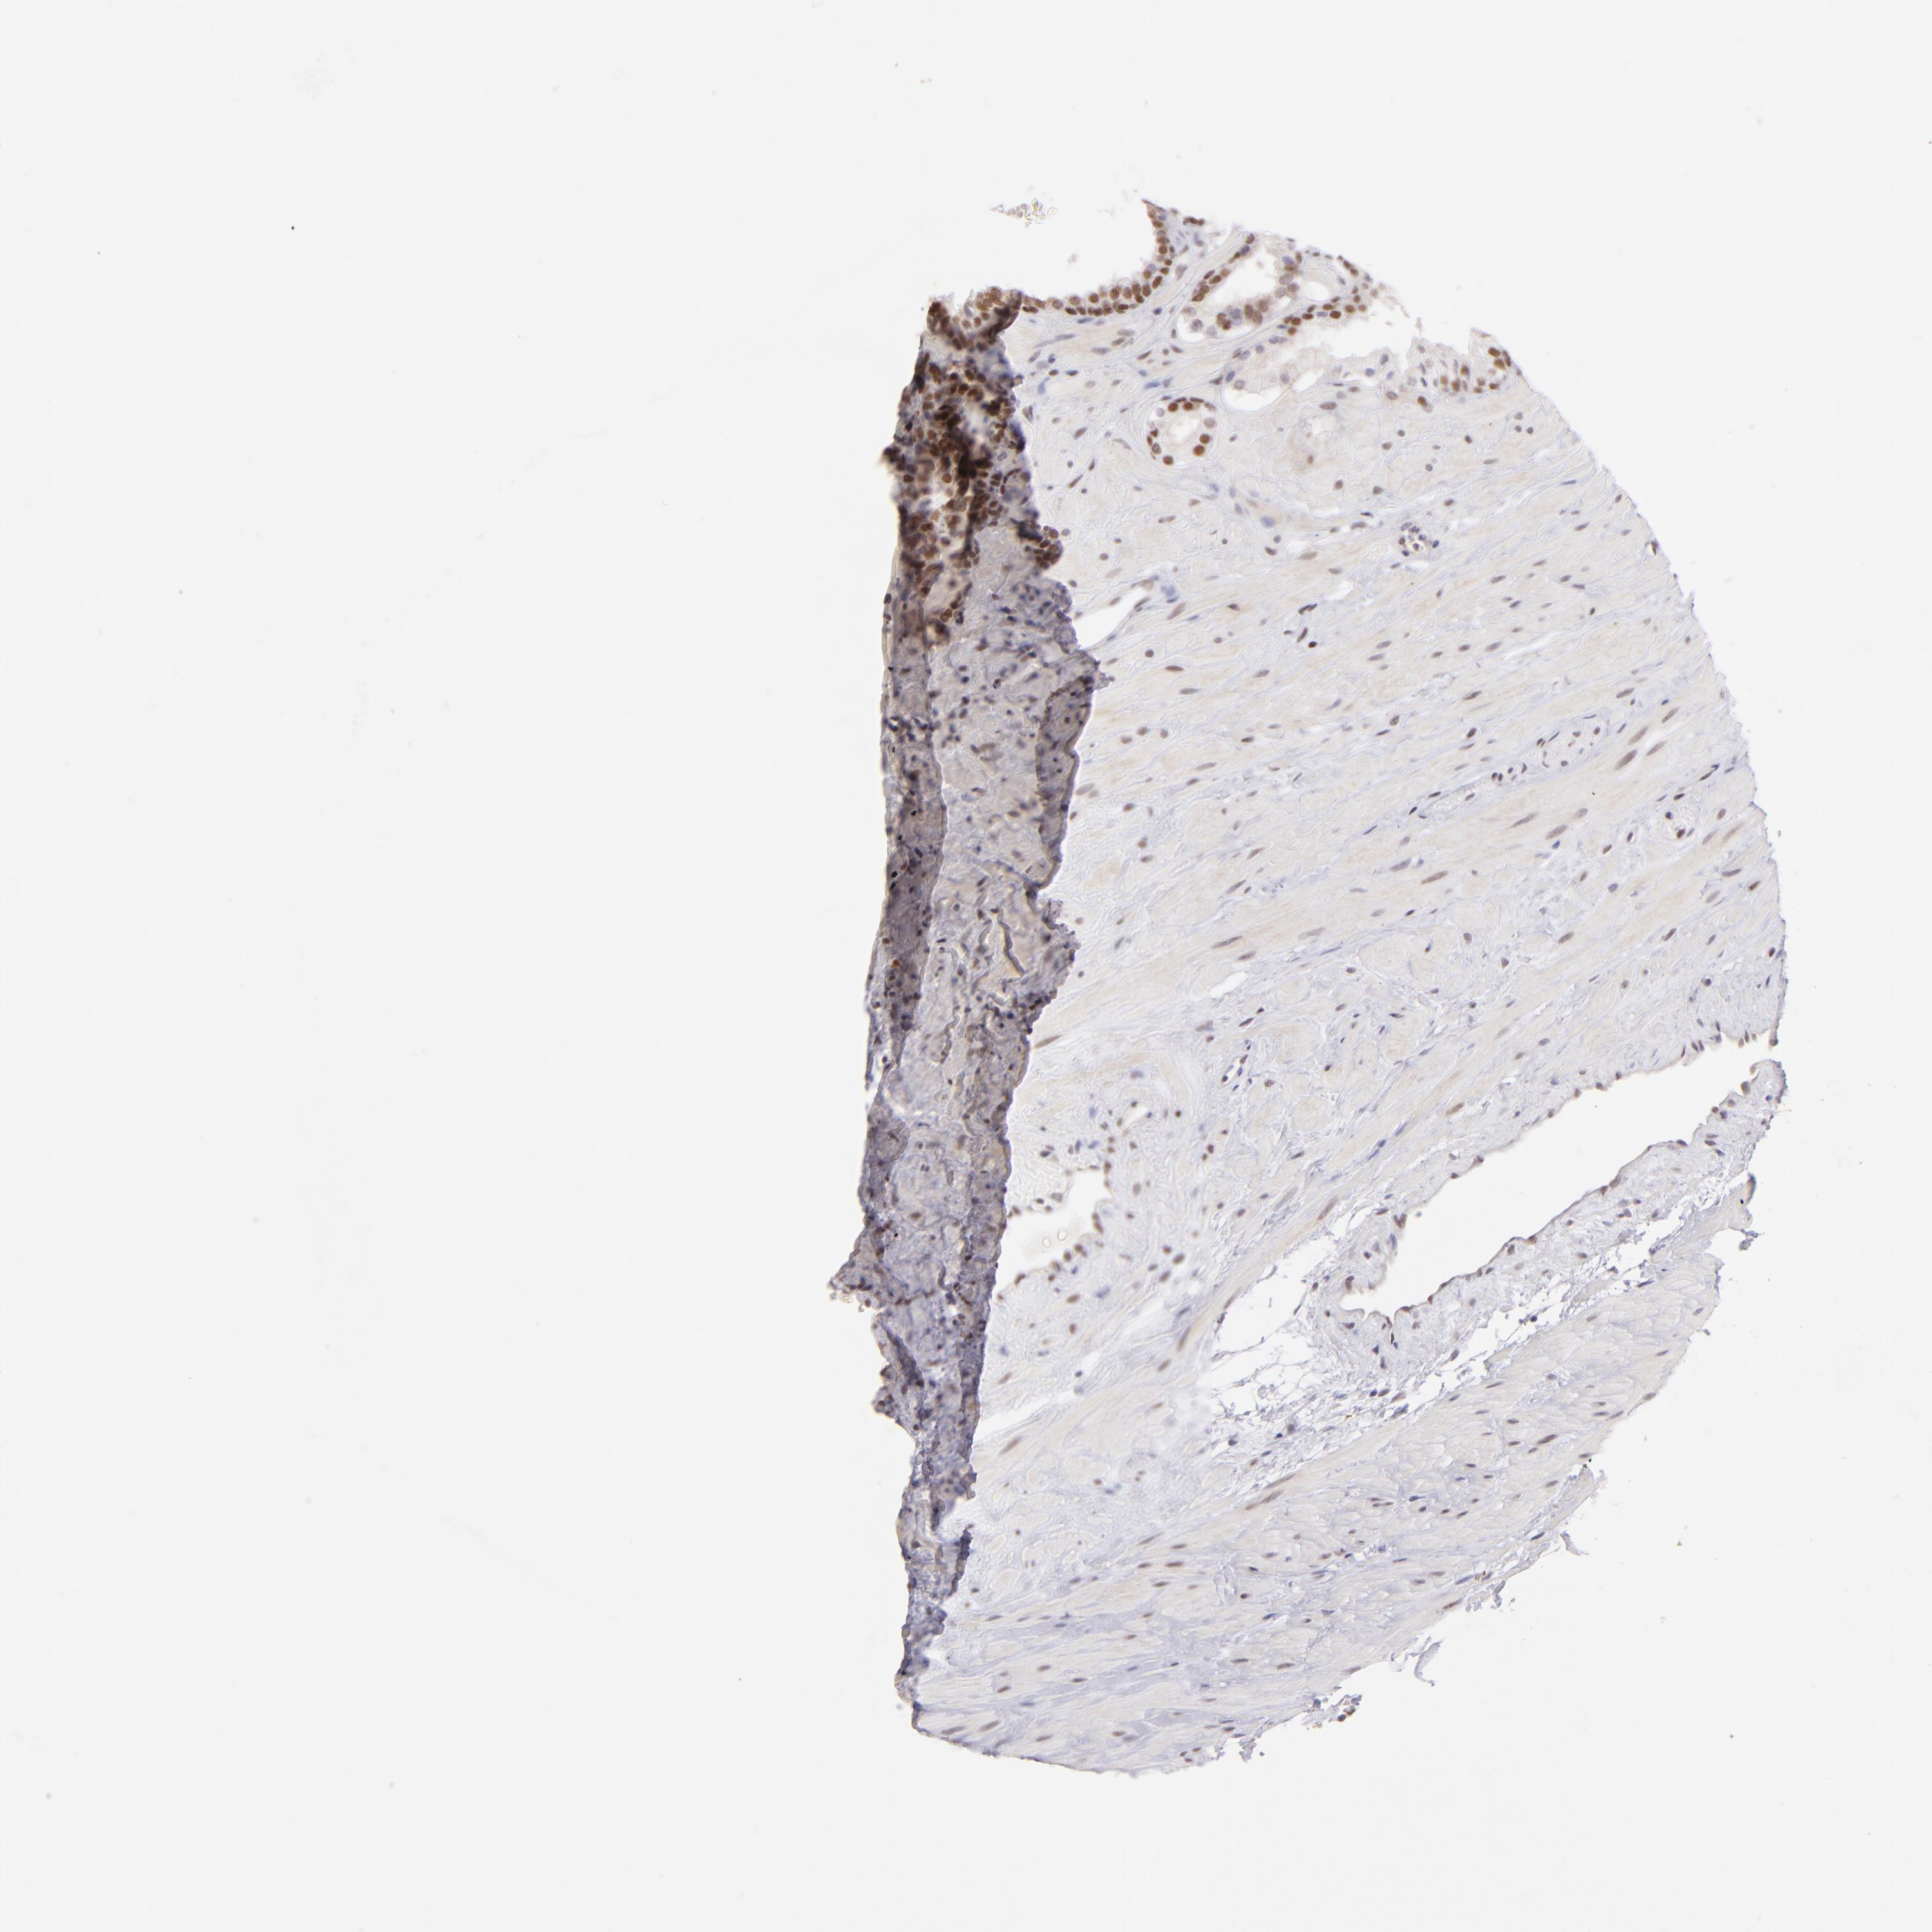

PROSTATE CANCER - Protein expressioni

A mouse-over function shows sample information and annotation data. Click on an image to view it in a full screen mode. Samples can be filtered based on level of antibody staining by selecting one or several of the following categories: high, medium, low and not detected. The assay and annotation is described here.

Antibody stainingi

Antibody staining in the annotated cell types in the current human tissue is reported as not detected, low, medium, or high, based on conventional immunohistochemistry profiling in selected tissues. This score is based on the combination of the staining intensity and fraction of stained cells.

Each image is clickable and will lead to virtual microscopy that enables deeper exploration of all samples and also displays staining intensity scores, fraction scores and subcellular localization as well as patient and tissue information for each sample.

Antibody HPA064323

Antibody CAB002608

Staining

High

Medium

Low

Not detected

Intensity

Strong

Moderate

Weak

Negative

Quantity

>75%

75%-25%

<25%

None

Location

Nuclear

Cytoplasmic/membranous

Cytoplasmic/membranous,nuclear

Adenocarcinoma, High grade

Adenocarcinoma, Low grade

Adenocarcinoma, Medium grade